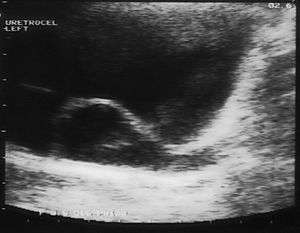

Since the advent of the ultrasound, most ureteroceles are diagnosed prenatally. The pediatric and adult conditions are often found incidentally, i.e. through diagnostic imaging performed for unrelated reasons.